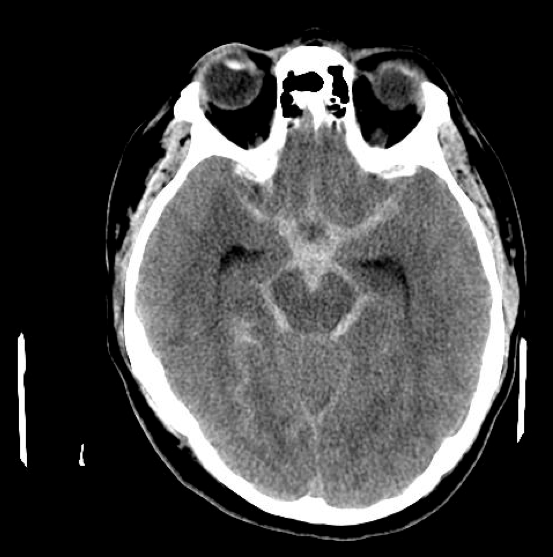

61 y/o man with history of poorly controlled HTN did not show up for work. His son found him on the floor, confused, speaking with slurred speech and unable to get up.

Exam showed dysarthria, moderate right sided weakness, and right sided sensory loss

• Vitals: 230/135, HR 104, RR 27

whats the etiology?

Hyaline aretherosclerosis

Infarct in the parietal cortex is likely to be due from:

an embolism